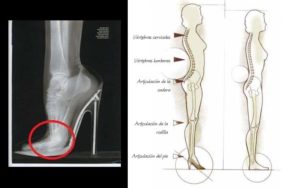

Тем не менее, врачи настоятельно советуют ограничить или полностью исключить ношение высокого каблука. Если этого не сделать, то может развиться лордоз, который ведет к нагрузке на мышцы спины и диски позвоночника.

- Женщинам придется сразу же расстаться с высоким каблуком. Ношение высокого каблука смещает центр тяжести тела, увеличивая нагрузку на поясничный отдел позвоночника, коленные и голеностопные суставы. Каблук, превышающий 4 сантиметра, считается высоким и при позвоночной грыже недопустим.

При ношении каблуков центр тяжести у женщины смещается вперёд, тем самым увеличивается нагрузка на голеностопный сустав, что в дальнейшем может привести к подворачиванию стопы внутрь. Поэтому идеальный размер каблука должен варьироваться от 3 до 5 сантиметров.

- Смещение центра тяжести. Если обратить внимание на женщину на каблуках, визуально можно обратить внимание на то, что каблук как бы откидывает тело женщины назад, благодаря которому она удерживает равновесие. Однако за счёт каблуков позвоночник может сильно прогнуться в пояснице, что вызывает неравномерную нагрузку на диски между позвонков.